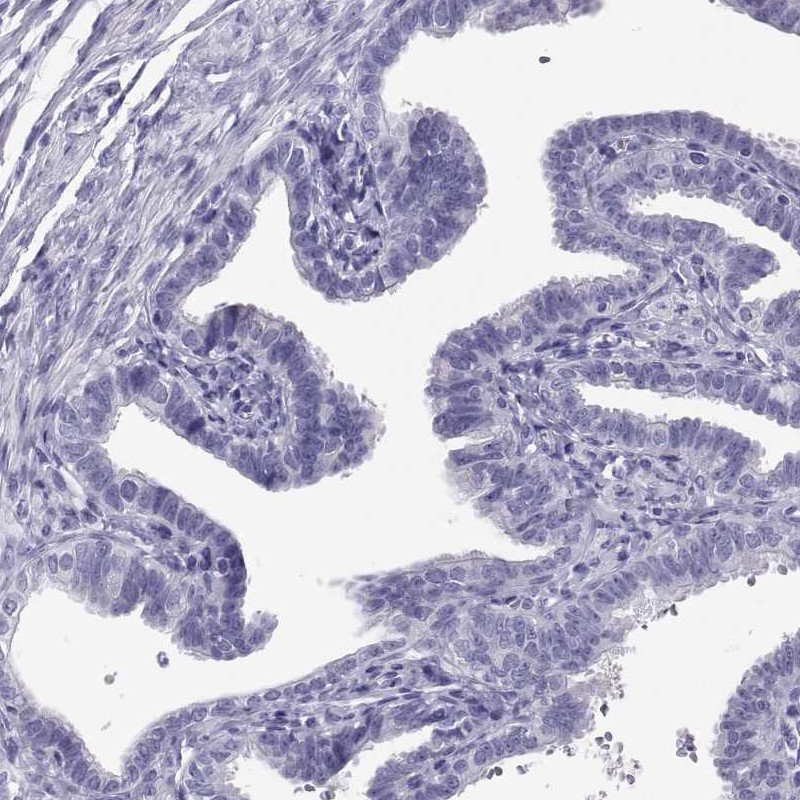

Immunohistochemistry analysis in human epididymis and fallopian tube tissues using Anti-RNASE12 antibody. Corresponding RNASE12 RNA-seq data are presented for the same tissues.